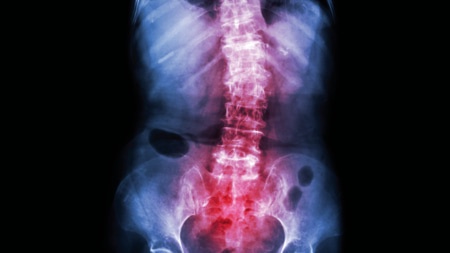

• Back pain